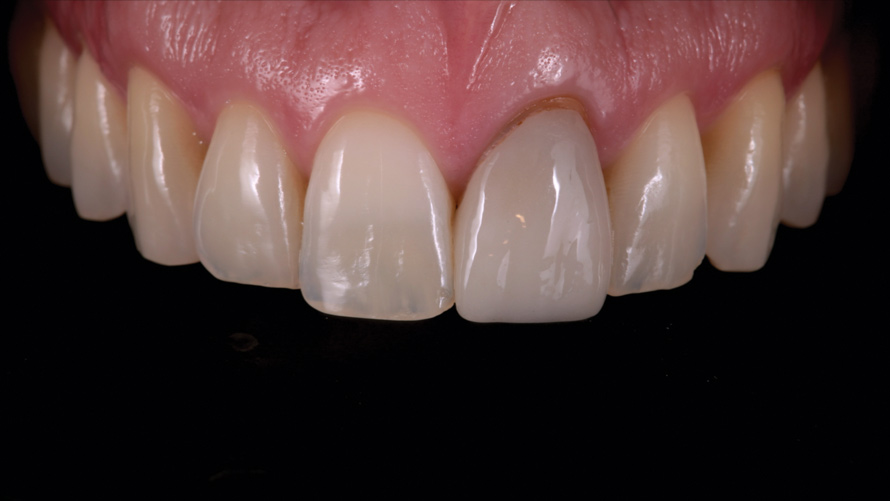

Eight weeks after the initial start of the walking bleach procedure, the final layered lithium disilicate crown was tried-in and evaluated for function and esthetics. Upon patient approval, the intaglio surface of the crown was etched for 20 seconds with a 9.6% hydrofluoric acid etchant, rinsed, and then scrubbed with a 37.5% orthophosphoric acid solution to clean out any ceramic debris. The crown was then placed into an ultrasonic bath of 91% isopropyl alcohol for 5 minutes, after which the intaglio surface was coated with silane and placed under a warm air dryer for 1 minute. A translucent self-adhesive resin cement was used to bond the final restoration to the preparation. The patients both stated that they approved of the form, function, and esthetics of the definitive restoration and that they were very pleased with the final results (Figure 13 through Figure 18). Routine periodic evaluations and radiographs were scheduled to monitor their oral health and esthetics.

(16.) Case 2: Retracted full-smile view of the definitive all-ceramic restoration on the maxillary left central incisor.

Figure 16